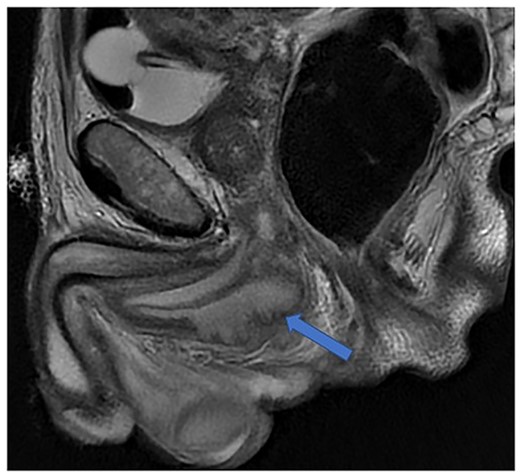

Imaging was suggestive of an infected Cowper’s syringocele. As the patient was clinically stable, a trial of antibiotic therapy was suggested. Repeat MRI a week later showed that the collection had extended into the corpus spongiosum, which now appeared expanded with the fluid density signal (Fig. 1). On a review, the urethral catheter was thought to be impairing potential drainage of the collection. It was removed, and a suprapubic catheter was inserted. Ultrasound guided aspiration failed to drain a significant amount of pus, which also grew S. anginosus. There was also radiological suspicion of a colovesical fistula. The patient was reviewed by the colorectal surgeons, who felt that as there were no other symptoms relating to the fistula, and the patient was physiologically frail, and defunctioning of the bowel would be inappropriate. Likewise, the patient was deemed too frail for any surgical management of the collection. He was discharged after a total of 6 weeks’ antibiotics. Repeat MRI 4 months later (Fig. 2) showed a smaller but persistent collection.

Case 1: sagittal and coronal T2-weighted images showing the collection (blue arrow) inferior to the prostate, and involving the corpus spongiosum (yellow arrow).